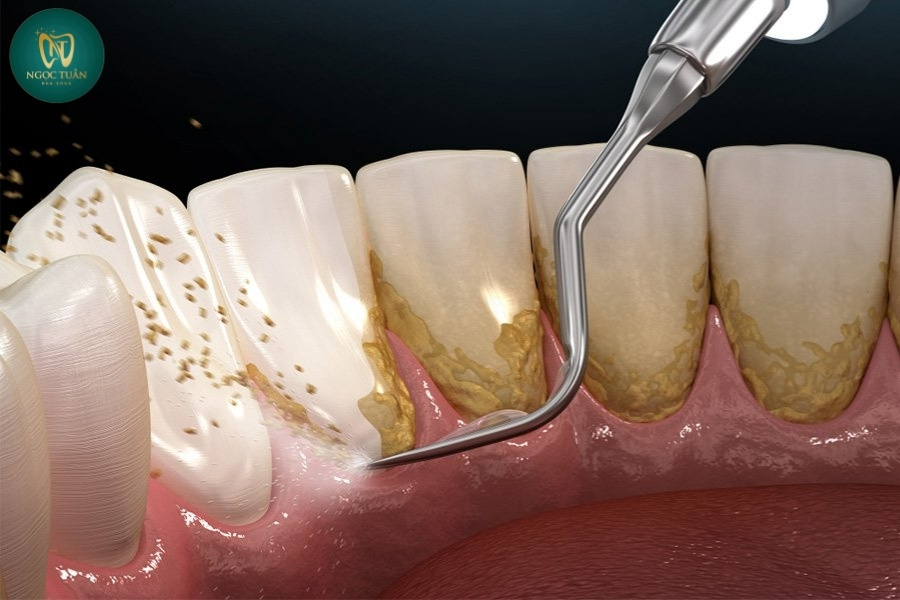

Vôi răng (cao răng) là những mảng bám chứa vi khuẩn, thức ăn thừa và khoáng chất từ nước bọt tích tụ trên bề mặt răng, đặc biệt là ở vùng viền nướu và kẽ răng. Khi không được làm sạch thường xuyên, những mảng bám này sẽ dần bị khoáng hóa, trở nên cứng và bám chặt vào bề mặt răng, tạo thành lớp vôi răng dày.

Quá trình hình thành vôi răng diễn ra qua các giai đoạn sau:

- Giai đoạn 1: Sau khi ăn uống, thức ăn và vi khuẩn sẽ tạo thành lớp màng mỏng gọi là mảng bám trên bề mặt răng.

- Giai đoạn 2: Nếu không được làm sạch đúng cách, mảng bám sẽ bắt đầu khoáng hóa do các khoáng chất có trong nước bọt.

- Giai đoạn 3: Sau khoảng 1-2 ngày, mảng bám bắt đầu chuyển hóa thành vôi răng và bám chặt vào chân răng, đặc biệt là ở những vùng khó vệ sinh như kẽ răng hoặc mặt trong của răng cửa dưới.

- Giai đoạn 4: Vôi răng phát triển dày hơn theo thời gian, tạo điều kiện thuận lợi cho vi khuẩn sinh sôi và phát triển, gây ra các vấn đề nghiêm trọng cho sức khỏe răng miệng.

Bước 3: Sử Dụng Máy Siêu Âm Để Loại Bỏ Vôi Răng

Tại Nha Khoa Ngọc Tuấn, việc cạo vôi răng được thực hiện bằng máy siêu âm hiện đại, mang lại hiệu quả vượt trội so với phương pháp thủ công truyền thống.

Cách hoạt động của máy siêu âm:

- Sử dụng sóng siêu âm với tần số cao để làm vỡ các mảng bám cứng đầu trên răng.

- Đầu máy siêu âm rung nhẹ, phá vỡ cấu trúc của mảng bám mà không gây tổn thương cho men răng hay nướu.

- Tích hợp hệ thống phun nước giúp làm mát vùng điều trị và rửa sạch các mảng vụn.